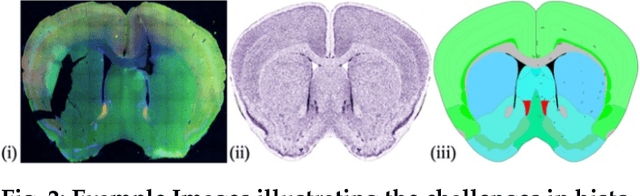

Abstract:Brain mapping research in most neuroanatomical laboratories relies on conventional processing techniques, which often introduce histological artifacts such as tissue tears and tissue loss. In this paper we present techniques and algorithms for automatic registration and 3D reconstruction of conventionally produced mouse brain slices in a standardized atlas space. This is achieved first by constructing a virtual 3D mouse brain model from annotated slices of Allen Reference Atlas (ARA). Virtual re-slicing of the reconstructed model generates ARA-based slice images corresponding to the microscopic images of histological brain sections. These image pairs are aligned using a geometric approach through contour images. Histological artifacts in the microscopic images are detected and removed using Constrained Delaunay Triangulation before performing global alignment. Finally, non-linear registration is performed by solving Laplace's equation with Dirichlet boundary conditions. Our methods provide significant improvements over previously reported registration techniques for the tested slices in 3D space, especially on slices with significant histological artifacts. Further, as an application we count the number of neurons in various anatomical regions using a dataset of 51 microscopic slices from a single mouse brain. This work represents a significant contribution to this subfield of neuroscience as it provides tools to neuroanatomist for analyzing and processing histological data.